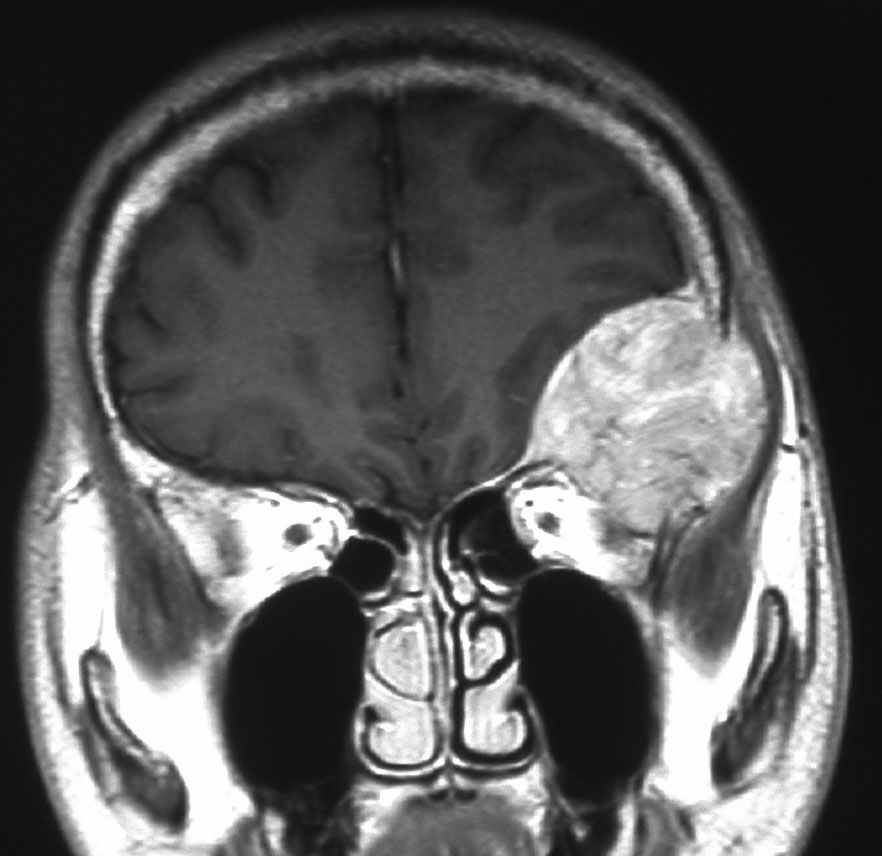

40代女性の後頭部傍矢状洞部の硬膜に発生したグレード3です。腫瘍周囲の強い浮腫のために,頭頂葉のゲルストマン症候で発症しました。術前診断は髄膜腫でしたが,腫瘍内部にのう胞(液体が溜まっている)があり,髄膜腫としては典型的な画像ではありません。右側の血管撮影にみられるように,上矢状洞が一部狭窄して腫瘍が浸潤している所見があり,腫瘍が濃染します。腫瘍の周囲の脳には出血がありました。大脳鎌と上矢状洞の壁を含めて全摘出しました。